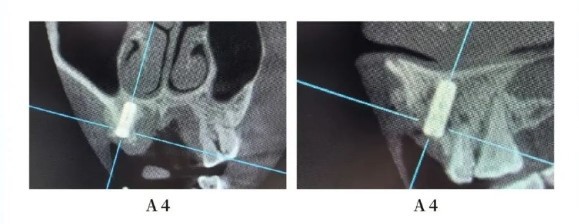

Postoperative Cone Beam Computed Tomography (CBCT)

Postoperative Summary: Implantation cases in the aesthetic zone of the anterior teeth have consistently been challenging and high-risk. Adequate preoperative design assessment, along with predicting the effects of bone augmentation and analyzing the type of bone deficiency, are crucial.

The Manners Apex dental implant, known for its classic bone-level cylindrical design, effectively dissipates stress in the implanted bone. A well-designed platform transfer contributes to achieving favorable aesthetic outcomes.